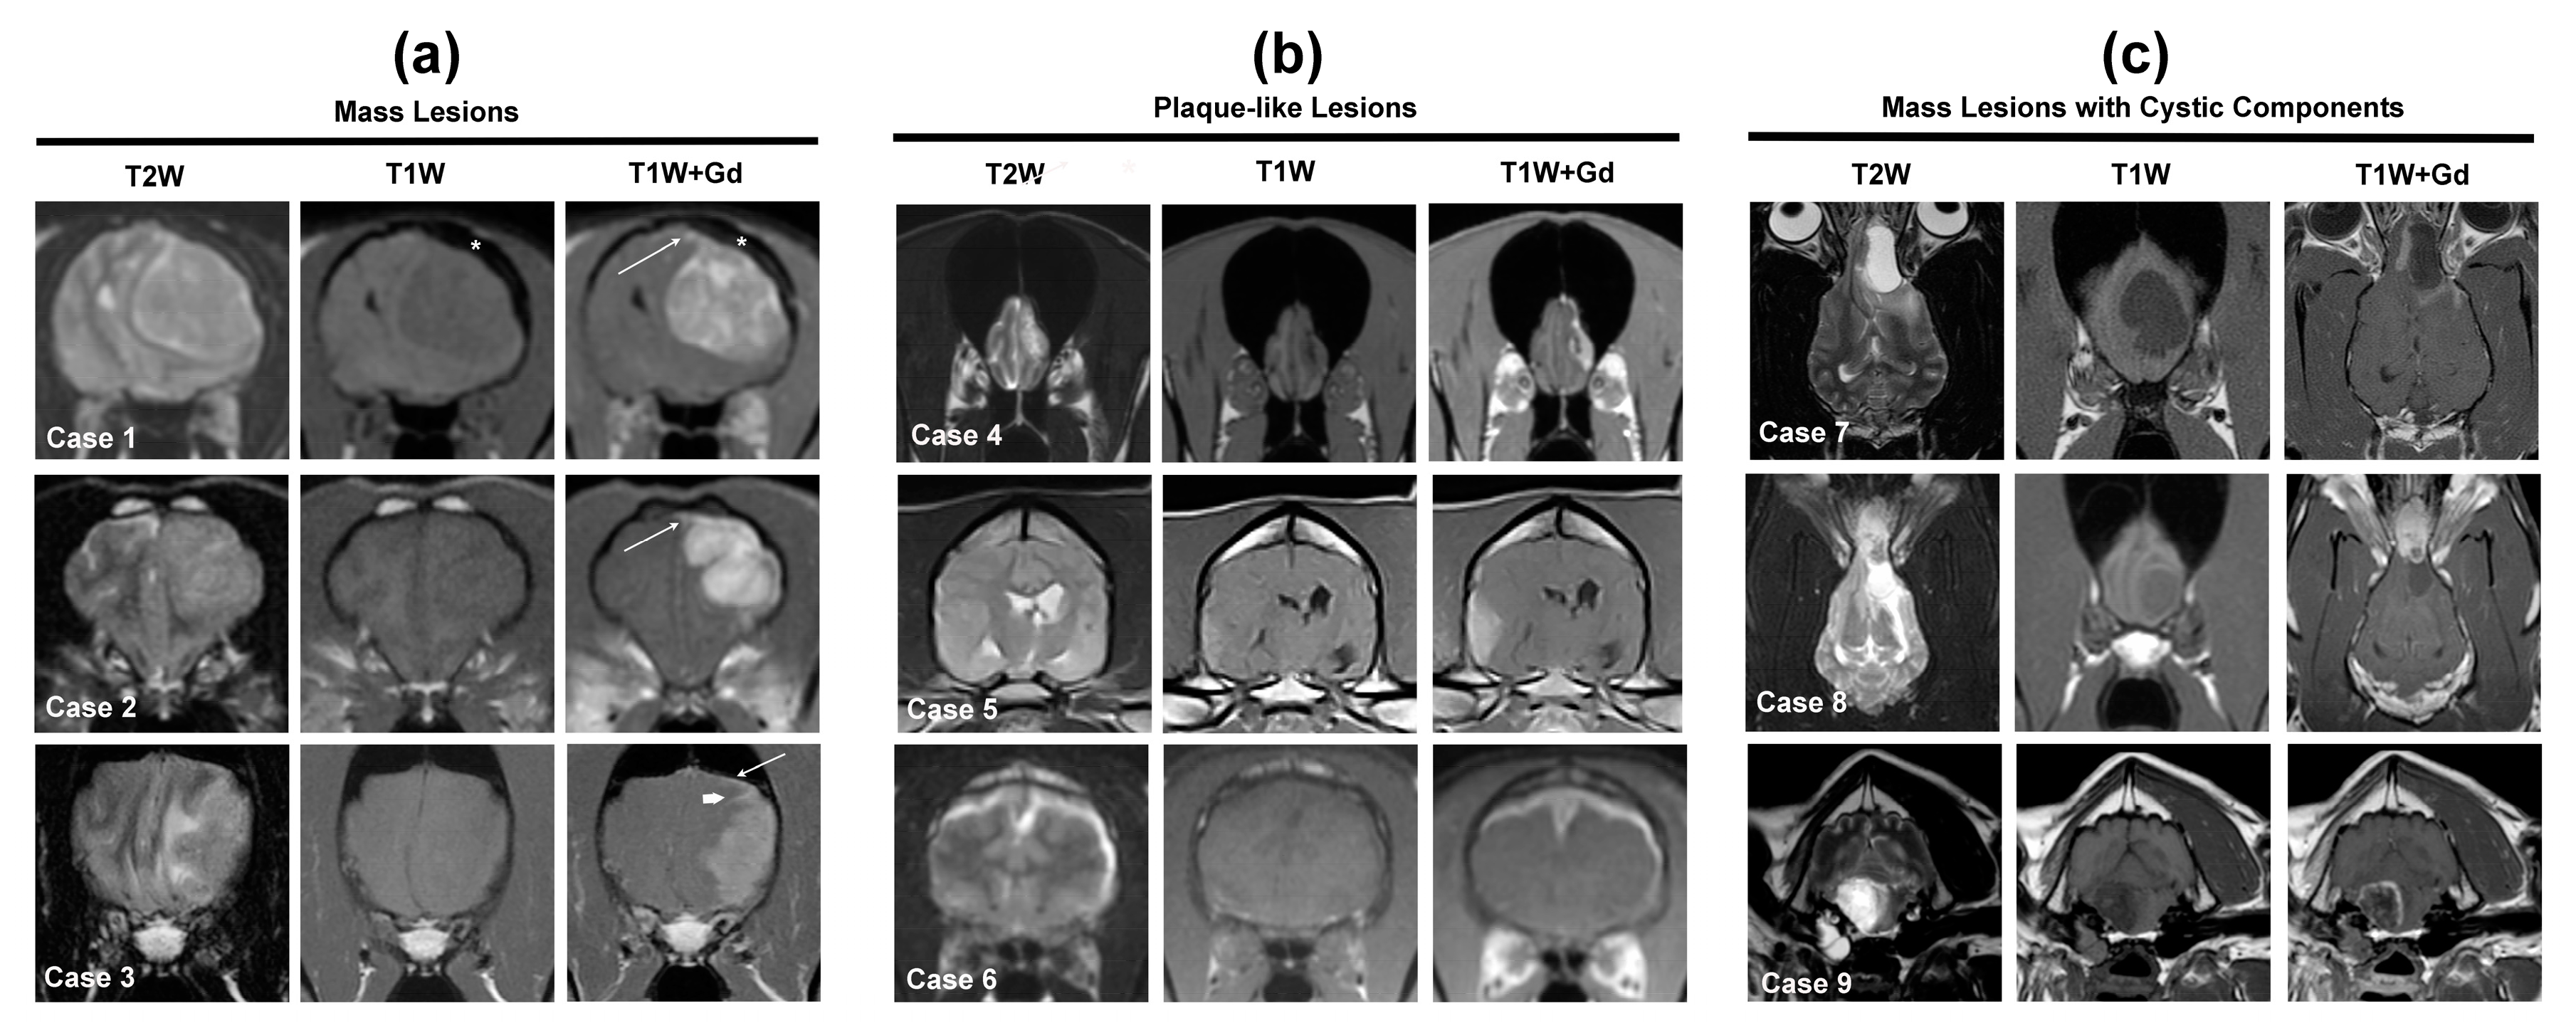

3.1. Solitary Extra-Axial, Meningeal Based Lesions

3.1.1. Meningioma

3.1.2. Histiocytic Sarcoma (HS)

3.1.3. Lymphoma